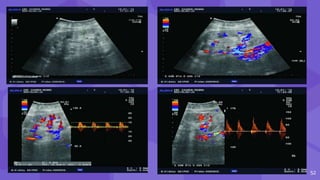

• #53 Doppler exam can show reduction of intrarenal arborization, lower flow rate values intrarenally with elevated RIs Fig. 43a B-mode ultrasound image. Kidney with moderately reduced and hyperechogenic parenchyma in long-term graft. Fig. 43b Color Doppler. Substantial reduction in intrarenal arborization, the same patient. Fig. 43cPulsed Doppler. Intrarenal atypical spectrum, extremely low flow rates of about 10 cm/s, the same patient. Fig. 43d Pulsed Doppler. Renal artery shows still normal flow rates of about 1 m/s, but with high-resistance waveform and almost no diastolic flow. All the above indicates chronic graft dysfunction